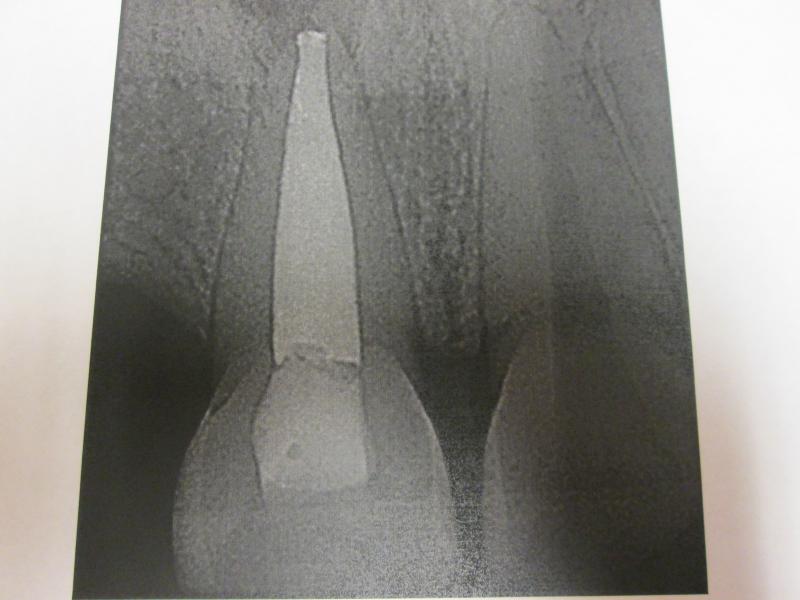

DR JET LOVES ROOT CANALS

General Dentist,  Performs Root Canals ONLY - Microscope Trained Dentist

"DR. JET'S MISSION IS TO PERFORM  ROOT CANALS FOR A REDUCED FEE USING THE LATEST TECHNOLOGY  AND TECHNIQUES TO SERVICE THE MANY PEOPLE WHO ARE UNINSURED OR UNDER-INSURED GIVING EVERYONE AN OPPORTUNITY TO SAVE THEIR TOOTH!"

ROOT CANALS by DR. JET (Jetepon Chiranand DDS)